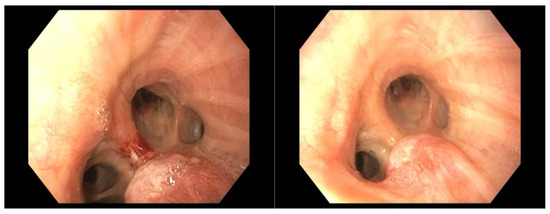

4.1. Case 1

4.2. Case 2